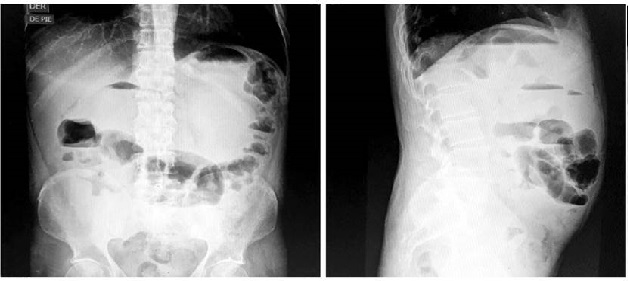

Paciente con evolución tórpida con un índice de Truelove-Witts de 19 puntos con brote moderado, colonoscopia con puntaje Mayo 2, presentó un cuadro de dolor abdominal de moderada a gran intensidad en la escala visual análoga (EVA) de 8/10, distensión abdominal, estreñimiento y vómitos posprandiales sugestivos de cuadro de oclusión intestinal. Se realizó una radiografía de abdomen en la que se observaron niveles hidroaéreos a nivel del colon transverso (Figura 3).